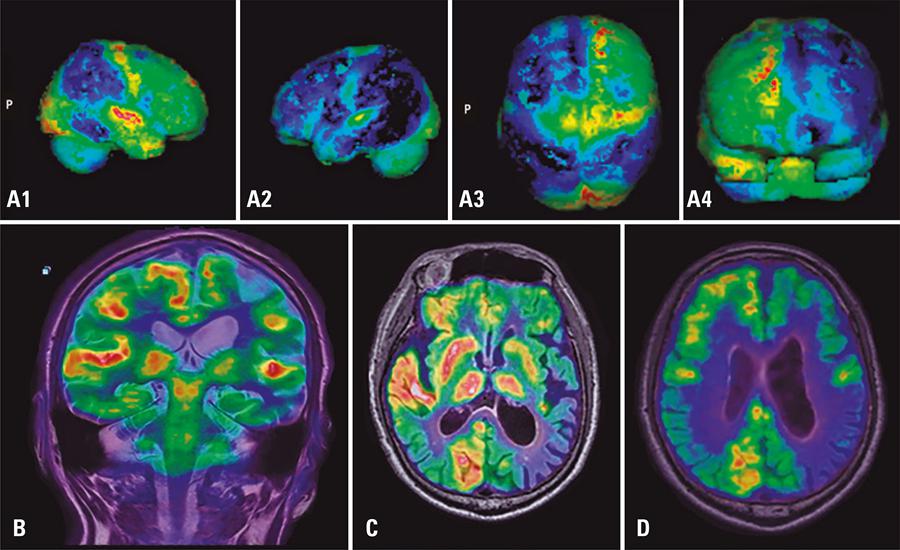

PET/RM: um novo método de imagem híbrida. Principais indicações clínicas e experiência preliminar no Brasil

Nos últimos anos, imagens médicas com tecnologias híbridas tornaram-se amplamente aceitas e utilizadas na prática clínica. O PET/RM possui vantagens importantes, incluindo excelentes contrastes e resolução, e menor radiação ionizante, em comparação ao PET/TC. Por isto, é uma modalidade promissora para exames de imagem de pacientes oncológicos, para avaliar o cérebro, cabeça e pescoço, o fígado e a pelve. O objetivo deste artigo foi analisar as situações clínicas que se beneficiariam de exames de PET/RM a partir de uma casuística. Destacamos o potencial desta técnica se tornar o método de imagem de escolha para doenças neurológicas e oncológicas que envolvam partes moles. Os aspectos clínicos de PET/RM e sua aplicação aos casos clínicos são ilustrados com exemplos da experiência inicial dos autores.